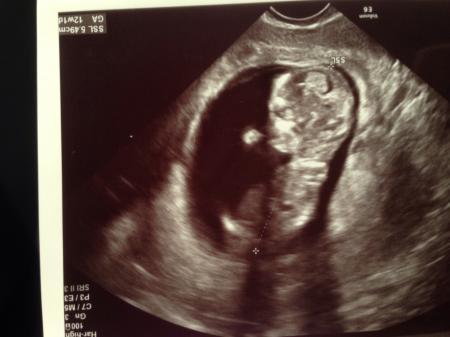

Hallo Mädels, Alles ist super :) Würmchen ist 5,5 cm groß und hat fleißig gezappelt. Wir sind total verliebt. Sofort als ich den Monitor gesehen hab, hatte ich das Gefühl, dass es ein Junge wird... bin gespannt. Bisher hatte ich das Gefühl, dass es ein Mädchen wird. Anbei 2 Fotos. Auf dem 1.Foto nuckelt es gerade; auf dem 2. kratzt es sich am Kopf :)

Bild zu Endlich Termin gehabt :) - Forum für Januar - Mamis